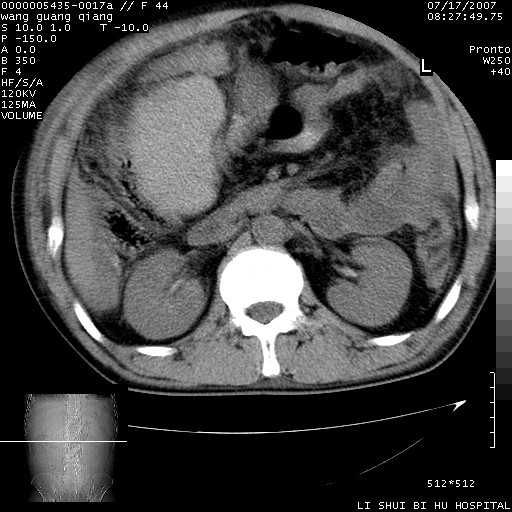

以下是引用dyqct在2007-7-18 10:46:00的发言:[br]胆囊明显增大,壁增厚,明显强化;后下方见大片高密度区,ct值68hu,无强化,周围见多数条纹状高密度影,边界不清。双膈下间隙、肝肾隐窝见带状及片状低密度区。[br]右侧胸壁后缘亦见新月形水样密度区。[br]考虑:1、急性胆囊炎伴周围出血;[br] 2、少量腹水、右侧少量胸腔积液。[br][br][本贴已被 dyqct 于 2007-7-18 10:48:47 修改过]